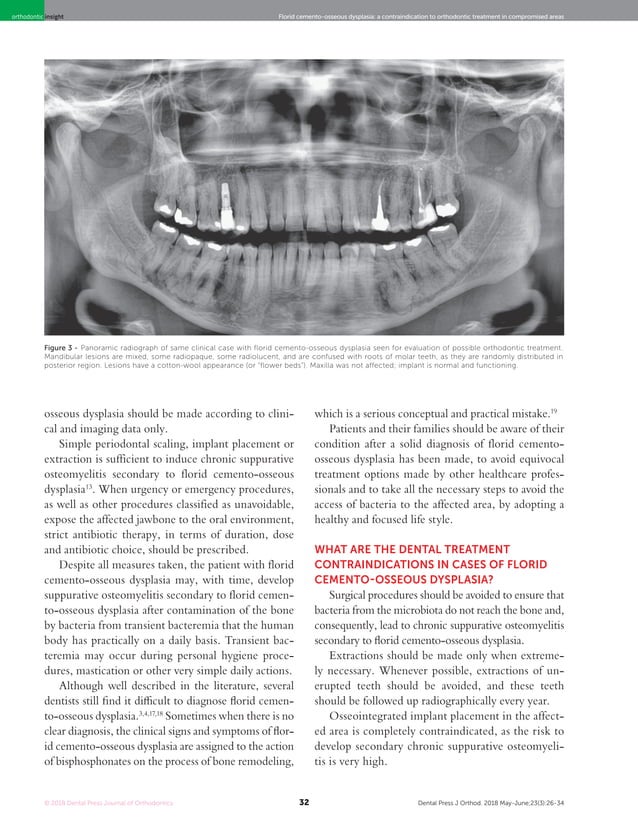

[PDF] Florid cementoosseous dysplasia a contraindication to Orthodontic Treatment And Cemento-Osseous Dysplasia A Case Report we compared clinical and radiological characteristics of symptomatic and asymptomatic patients. Orthodontic Treatment And Cemento-Osseous Dysplasia A Case Report.